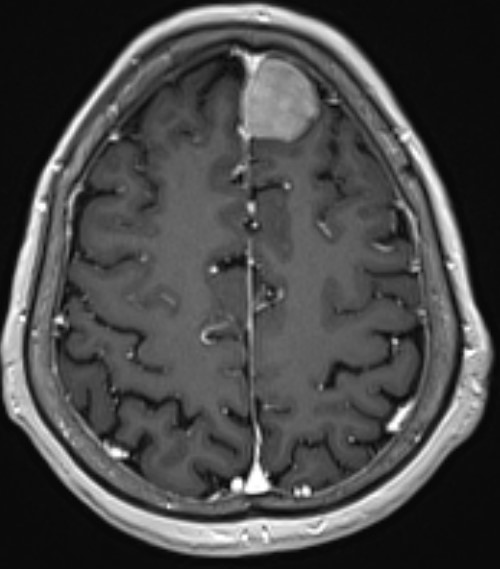

完善术前检查在全麻下行左额开颅肿瘤切除术

手术精要:1 肿瘤基底在大脑镰,切口过中线,骨窗显露矢状窦边缘;2  翻开硬膜及切除肿瘤时注意肿瘤周围尤其是肿瘤表面的引流静脉的保护;3 肿瘤切除策略锐性分离,分块切除,优先阻断肿瘤基底血供

术后病理提示脑膜瘤,混合型

患者恢复良好无神经功能障碍,一周顺利出院